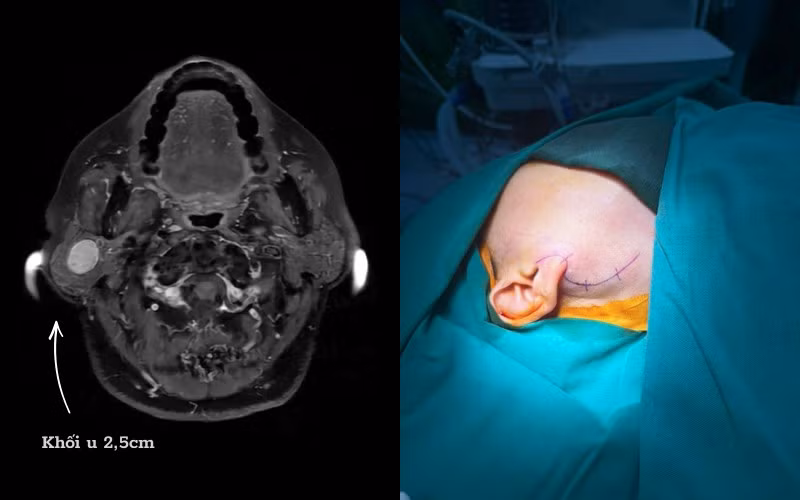

Trường hợp bệnh nhân D. là ví dụ điển hình, người bệnh phát hiện khối u tuyến mang tai phải từ nhiều năm trước, có biểu hiện sưng lệch vùng góc hàm, thỉnh thoảng đau tức. Dù đã được chỉ định phẫu thuật từ sớm nhưng bệnh nhân liên tục trì hoãn do lo ngại có nguy cơ liệt mặt sau mổ.

U tuyến nước bọt mang tai của chị D có vị trí phức tạp - Ảnh BVCC

Tiếp nhận thăm khám cho bệnh nhân D., ThS.BSNT Nguyễn Xuân Quang - Trưởng khoa Tai mũi họng và Phẫu thuật Đầu Cổ, Bệnh viện Đa khoa Hồng Ngọc cho biết, việc người bệnh trì hoãn điều trị trong thời gian dài khiến khối u tiếp tục phát triển, làm tăng nguy cơ chèn ép và tổn thương dây thần kinh mặt, điều này sẽ khiến ca mổ trở nên phức tạp hơn.

Ca phẫu thuật của bệnh nhân D. kéo dài khoảng 3 giờ, kết quả thành công tốt đẹp. Khối u được lấy trọn vẹn mà không cần cắt bỏ toàn bộ tuyến mang tai. Sau mổ, người bệnh D. hồi phục tốt, không ghi nhận liệt dây thần kinh mặt.

Đặc biệt, gương mặt cân đối, không méo lệch, chức năng vận động và yếu tố thẩm mỹ được bảo tồn nguyên vẹn.